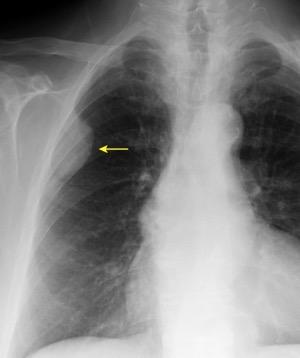

De los pacientes con Tumor de Pancoast

1,7% tienen una radiografía de tórax normal

Fletcher F et al. The normal chest radiograph in bronchial carcinoma. Br Med J. 1976